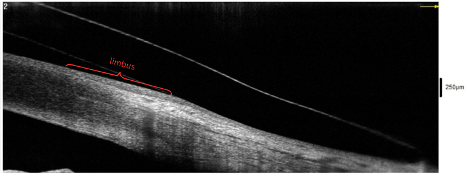

The ideal fit of a scleral lens shows a central clearance of around 200 µm, no limbal touch, and edge alignment with the sclera. On OCT, the limbus can be seen as a reflectivity change in the cornea (see Figure 4). This area should not be touched by the lens but should also not have excessive clearance, as negative pressure forces can pull the conjunctiva into that zone and cause conjunctival prolapse (see Figure 5) or excessive limbal hyperemia. OCT can also assist with evaluation of edge alignment. Appropriate edge alignment will be shown when the conjunctiva overlies half or more of the edge thickness, as seen in Figure 6, but does not fold over the edge of the lens.